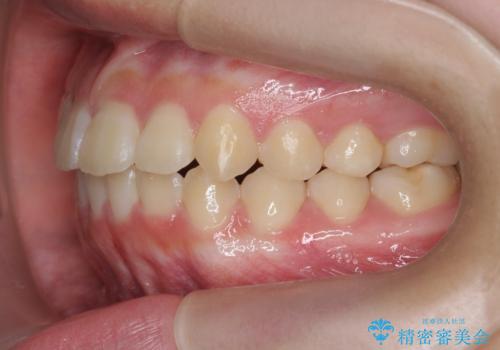

インビザラインで行う八重歯の治療

- 笑った時に目立つ八重歯の矯正治療を求めて来院されました。

マイクロインプラントを用いた臼歯の後方牽引、およびゴムかけ等の付加処置を駆使して八重歯の治療を行っていきます。

しっかりとゴムかけを頑張っていただいたおかげで、上顎臼歯の後方移動が達成されしっかりとした噛み合わせの構築と、八重歯の治療を達成することができました。